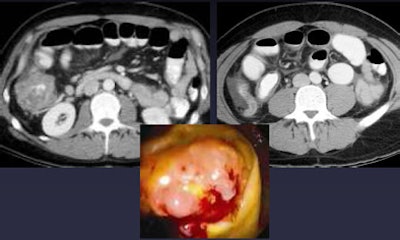

| Tumors can cause obstructive appendicitis, especially in elderly populations, as in the cecal cancer, above, causing acute appendicitis. Below, alternative diagnosis of an intussuscepted appendicele. All images courtesy of Dr. Perry Pickhardt. |